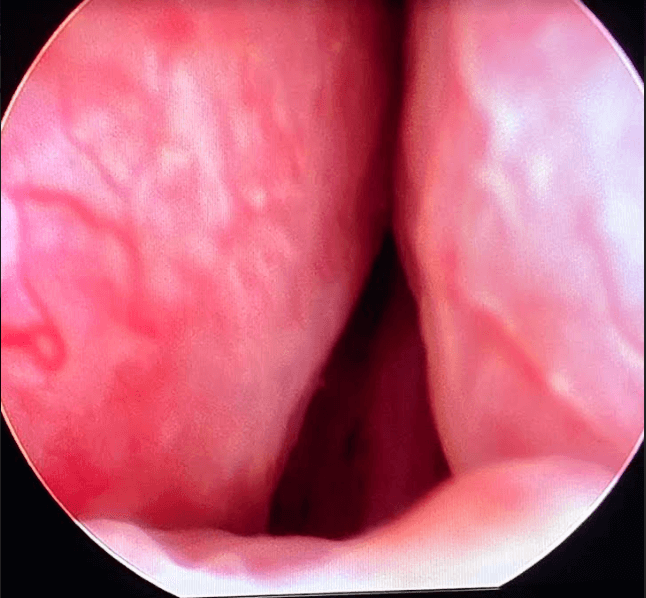

Before & After Pics of UroLift in Atlanta

Procedure

Procedure Details